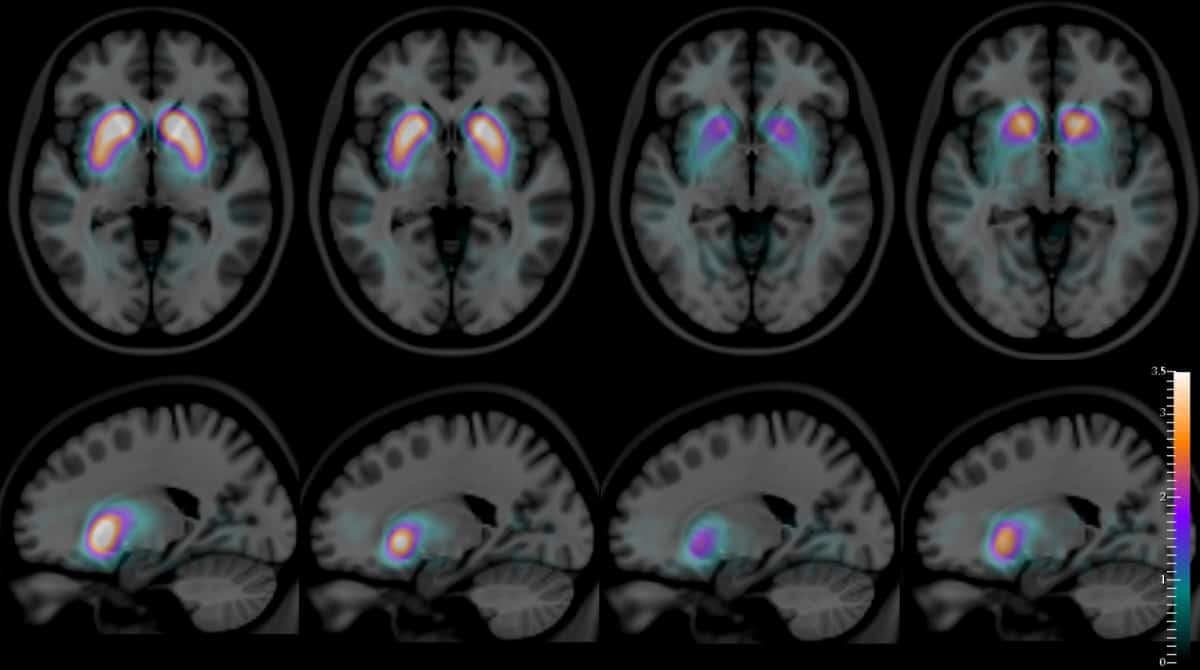

Situé au milieu du cerveau, ce petit organe fonctionne comme un chef d'orchestre qui contrôle toutes les glandes de votre corps. Votre médecin peut demander une IRM hypophysaire après certaines anomalies...